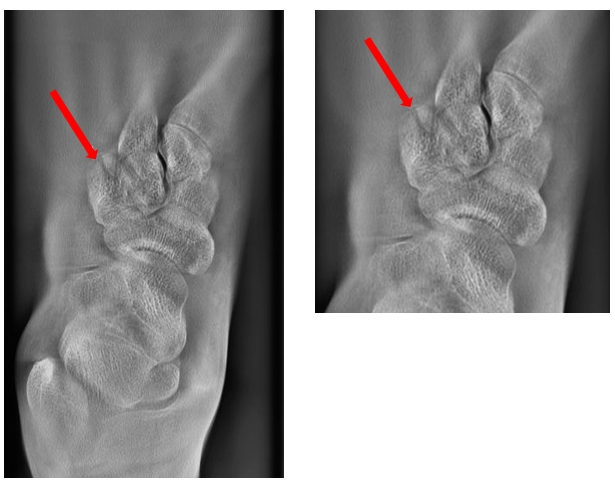

病例二:女,31岁。右手摔伤。

通过断层融合图像分析,为豆状骨骨折。